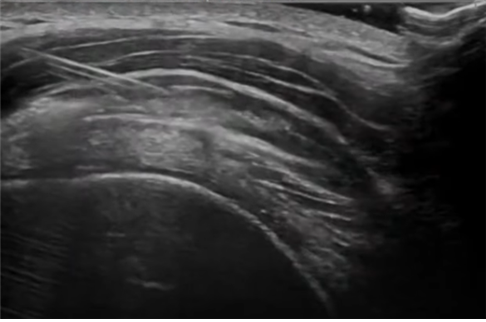

제너럴 일렉트릭사(GE)의 최신모델인 LOGIQ TOTUS를 통하여 초음파 진단 및 초음파가이드 약침요법(ultrasound-guided pharmacopuncture)을 시행합니다.

초음파 검사는 방사선 노출 위험이 없어 안전성은 물론, 실용성이 뛰어나 한의학 분야에서도 효과적인 시술 보조 기기로 활용되고 있으며 해당 기기를 사용하면 주요 신경과 혈관을 시각화해 손상 위험을 줄일 수 있고 정확한 부위에 침이나 약침을 시술할 수 있어 치료 효과 역시 극대화할 수 있습니다.

초음파 가이드 약침요법(ultrasound-guided pharmacopuncture)은 한의학적 원리에 따라 한약 성분을 추출·정제해 만든 약침액을 초음파 장비를 사용해 시술 부위를 실시간으로 확인하면서 보다 정확하고 안전하게 약물을 병변 부위에 주입하는 치료법입니다.

고해상도 초음파 장비를 사용해 혈관·신경·손상부위·염증부위에 약침을 주입합니다. 약침 성분에 따라 기혈 순환 촉진, 어혈 제거, 염증 완화, 조직 재생 촉진 등의 효과를 기대할 수 있습니다.